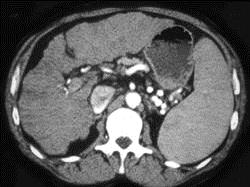

男,71岁,继往有肝炎病史,CT检查如图,请选择最佳诊断 ( )A、肝转移瘤B、肝色素沉着症C、肝癌D、肝硬化E、脂肪肝

问题 男,71岁,继往有肝炎病史,CT检查如图,请选择最佳诊断 ( )

选项 A、肝转移瘤 B、肝色素沉着症 C、肝癌 D、肝硬化 E、脂肪肝

答案 D